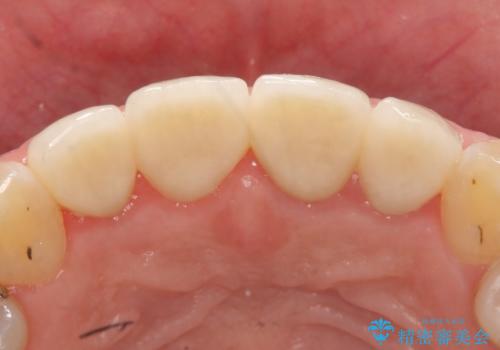

- 前歯の色・形を綺麗にしたいといらっしゃった方の症例です。

左上1、2の再根管治療終了後、オールセラミッククラウン(スペシャル)による補綴を行いました。

前歯の補綴ではオールセラミッククラウンを希望される患者様が多いですが、オールセラミッククラウンの中でも、エコノミー、スタンダード、スペシャル、エクセレントとランクがあります。

その中でも特に審美性が高いのがスペシャル、エクセレントです。スペシャル、エクセレントは口腔内写真をもとに熟練の技工士が、患者様の口腔内に合わせたオーダーメイドのクラウンを製作致します。